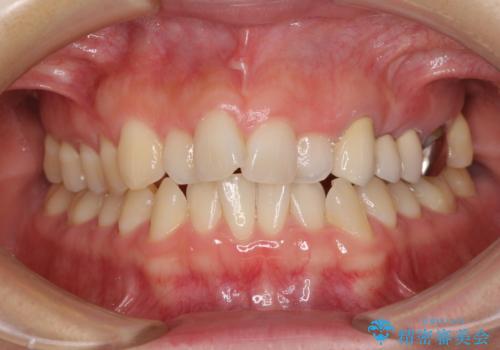

- 上下前歯のデコボコと銀歯のブリッジを気にして来院された患者様です。

装着されているブリッジを切断して矯正治療を行うことや、手間をかけずに早めに治療を終えたいとのことで、目立たないワイヤー装置による矯正治療を行うこととしました。